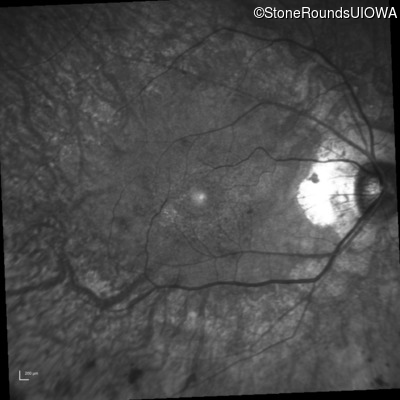

Infrared Fundus Photograph - Left - 20/25 sc

Exemplar